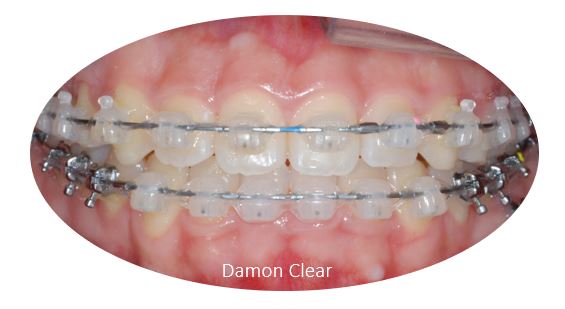

'자가결찰교정장치'에 해당하는

데이몬클리어 교정은

일반 브라켓에 비해 마찰이 적어 치아 이동이 빠르고,

철사의 교정력이 치아에 효과적으로 전달되어 통증이 비교적 적습니다.

또한 브라켓이 둥글둥글한 형태로 이물감이 적고 치석 침착이 적습니다.

또한 치아 색상과 유사해 심미적으로 장치 노출에 대한 걱정을 줄여줍니다.

데이몬 클리어 교정장치는

교정장치로 워낙 유명한 미국 Ormco사의

'자가 결찰 방식' 으로 치아와의 마찰력이 적고 적은 힘이 일정하게 지속되어

비교적 통증이 적고 심미적인 것이 장점입니다.

자가결찰브라켓(Self ligating Bracket) 이 무엇인가요?

와이어와 브라켓을 고무링이나 얇은 철사로 묶는 것이 아니라

여닫이 뚜겅을 통해 와이어를 연결하는 장치 입니다.

자가결찰방식의 교정으로는

데이몬 교정과( Damon) 과 클리피씨 교정 (Clippy-C) 이 대표적입니다.

자가결찰 브라켓의 장점은

고무링이나 철사를 이용하지 않고 뚜껑을 여닫는 슬라이딩 방식으로

마찰력이 적어 교정기간이 단축될수 있고

매달 오시는 진료시간도 단축됩니다.

또 결찰 와이어로 인해 잇몸을 찌르거나

철사가 풀어지는 상황을 예방할 수 있습니다.